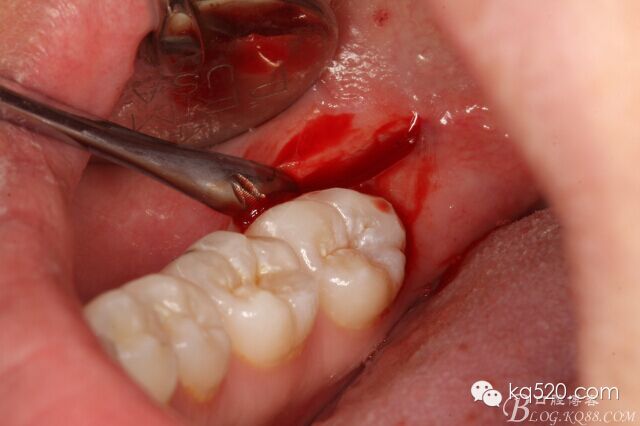

圖5.偏頰側、做直線微切口,切口約1cm。

圖6.翻小瓣

圖7.暴露48合面

圖8.小牙挺挺松48.

圖9.拔除48.

手術特點: 小切口、術后 反應輕、無腫脹、不縫合、手術時間短。